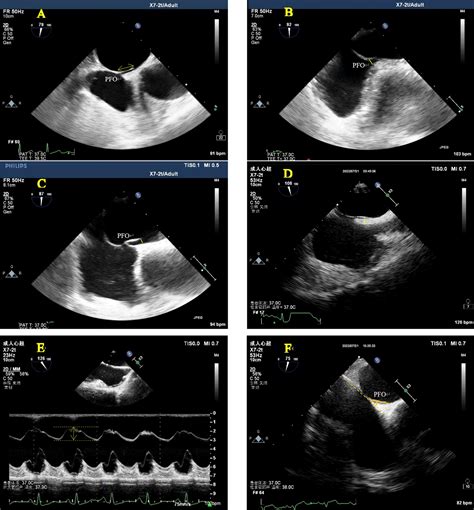

1470×1333

wjgnet.com

Novel way of patent foramen ovale detection and percutaneous closure b…

1013×1166

frontiersin.org

Frontiers | Only transesophageal echocardio…